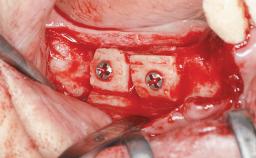

Ridge Preservation and Implant Placement for a Fixed Dental Prosthesis After a Car Accident

Bone Augmentation Horizontal|Simultaneous|Sinus Floor Elevation|Staged

Augmentation Materials Xenogenous|Membrane